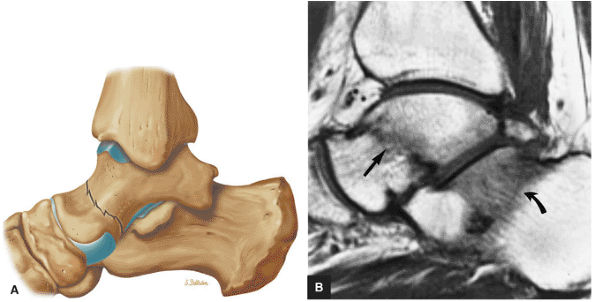

FIGURE 5.26 ● Coronal anatomy of the ankle and foot. (A) The calcaneofibular ligament (CFL) is identified by finding its origin at the inferior tip of the lateral malleolus. The posterior inferomedial course of the CFL is followed on three or four consecutive coronal images moving posteriorly through the ankle, to its insertion on the posterolateral calcaneus. Optimal evaluation of the CFL involves examining its full course on successive images in both the coronal and sagittal plane for tears, sprain, or scarring. (B) The medial cord of the plantar aponeurosis is normally slightly thicker than the lateral cord, and this mild asymmetry in thickness should not be misinterpreted as plantar aponeurosis scarring or plantar fasciitis. On successive coronal images, the course of the plantar aponeurosis should be followed back to its insertion on the inferior calcaneus and evaluated for the presence of thickening, decreased signal suggestive of scarring, increased signal indicative of plantar fasciitis, and tears. (C) Coronal images are optimal for viewing the lateral process of the talus, which is a frequent site of fractures that are occult on plain films. Fractures of the lateral process of the talus are most common in patients with snowboarding injuries. (D) The talar dome and tibial plafond are optimally visualized on coronal images. They are assessed for the presence of subchondral edema and cystic change with overlying chondral abnormalities. Close attention should be directed to the extreme anterior and posterior margins of the cartilage-bearing articular surfaces of the talar dome and tibial plafond to avoid overlooking osteochondral lesions at these locations. (E) The origin of the anterior talofibular ligament (ATFL) is found at the anterior distal tip of the lateral malleolus, and the ATFL is followed anteriorly on two or three successive coronal images to its insertion at the anterior lateral margin of the talus. (F) The deltoid ligament is optimally visualized in the coronal and axial planes. Tears of the deltoid manifest as loss of fiber striation or diffuse amorphous hyperintensity in the ligament on fluid-weighted sequences. Partial tears are more common than complete tears. (G) Focal fatty atrophy and denervation of the plantar flexor muscles of the foot (abductor digiti minimi, flexor digitorum brevis, and abductor hallucis) may indicate neuropathy involving the tibial nerve or its branches. (H) At the level of the anterior aspect of the talus and calcaneus, the peroneal tendons and flexor tendons turn from their cranial—caudal course to travel an anterior-to-posterior course along the plantar aspect of the foot. The distal portions of the tendons should be examined along the plantar aspect of the foot on successive coronal images for evidence of tendinosis and tears. (I) The base of the fifth metatarsal is a common location for fractures and is often visualized within the FOV on ankle MR exams. (J) At the level of the navicular, the flexor digitorum longus (FDL) and flexor hallucis longus (FHL) tendons run side by side, with the FDL medial to the FHL. Anterior to this level on successive coronal images, the two tendons cross, with the FHL medial to the FDL as the FHL courses to its insertion on the great toe. (K) Stress fractures of the navicular are commonly vertical in the midline of the navicular, an appearance that is well characterized on coronal images. (L) Contusions, stress-related edema, fractures, and degenerative arthritis of the midfoot bones and joints are common causes of midfoot pain and are often optimally identified on fluid-sensitive sequences.